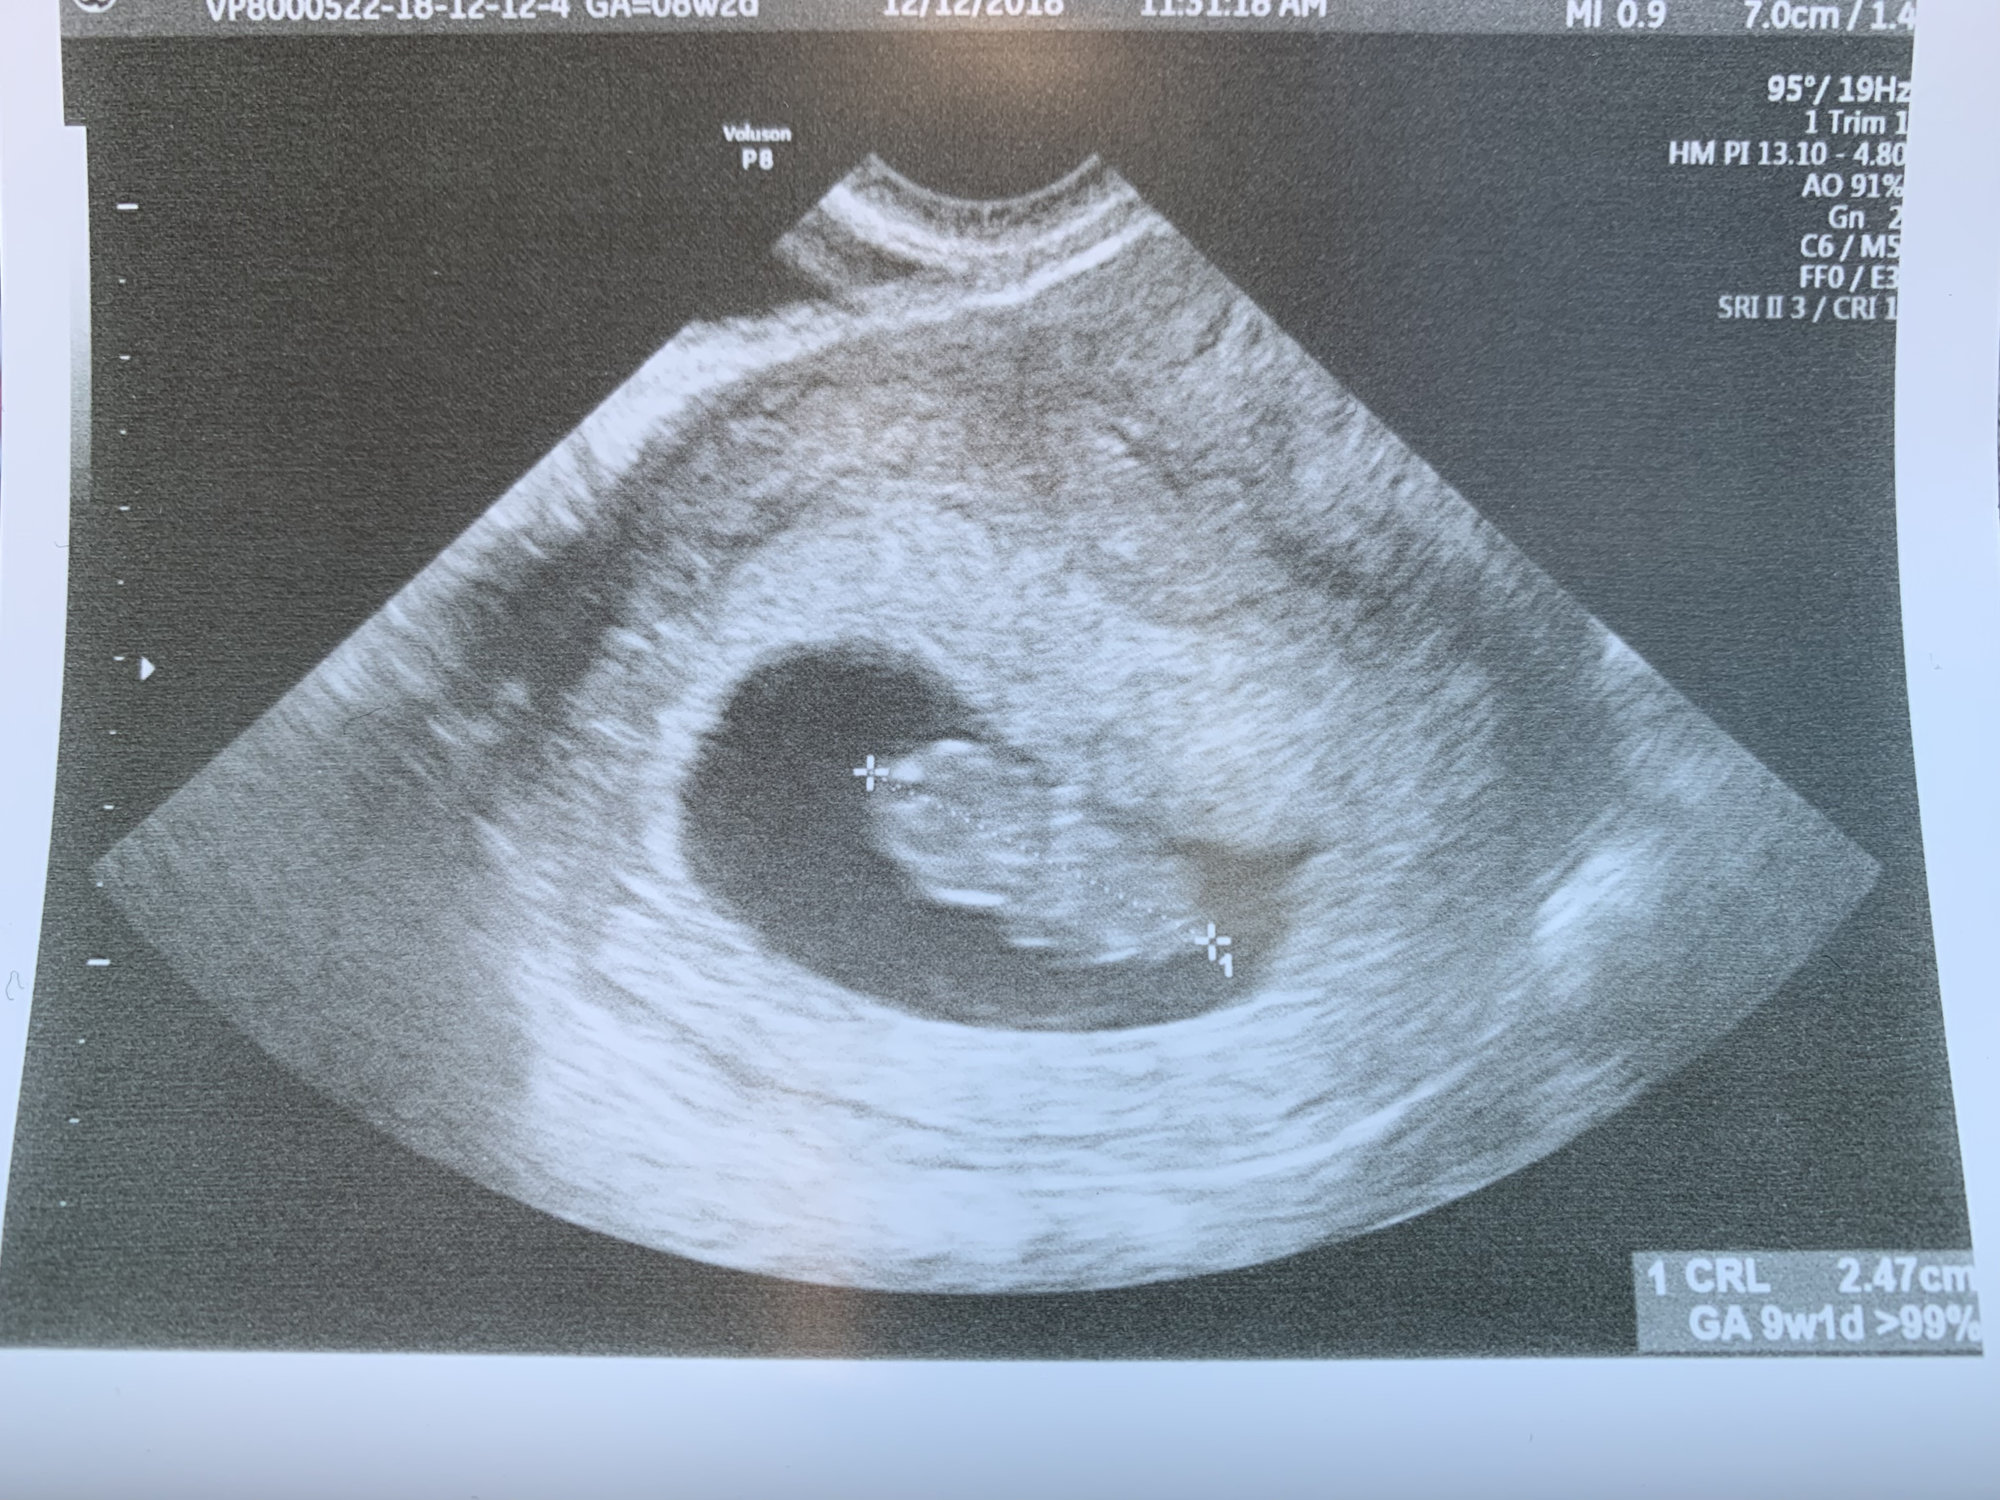

Second ultrasound! I’m 9 weeks today and baby is measuring 8wks 4 days. Within the margin so they’re keeping my 7/11 due date. Strong heartbeat at 178!